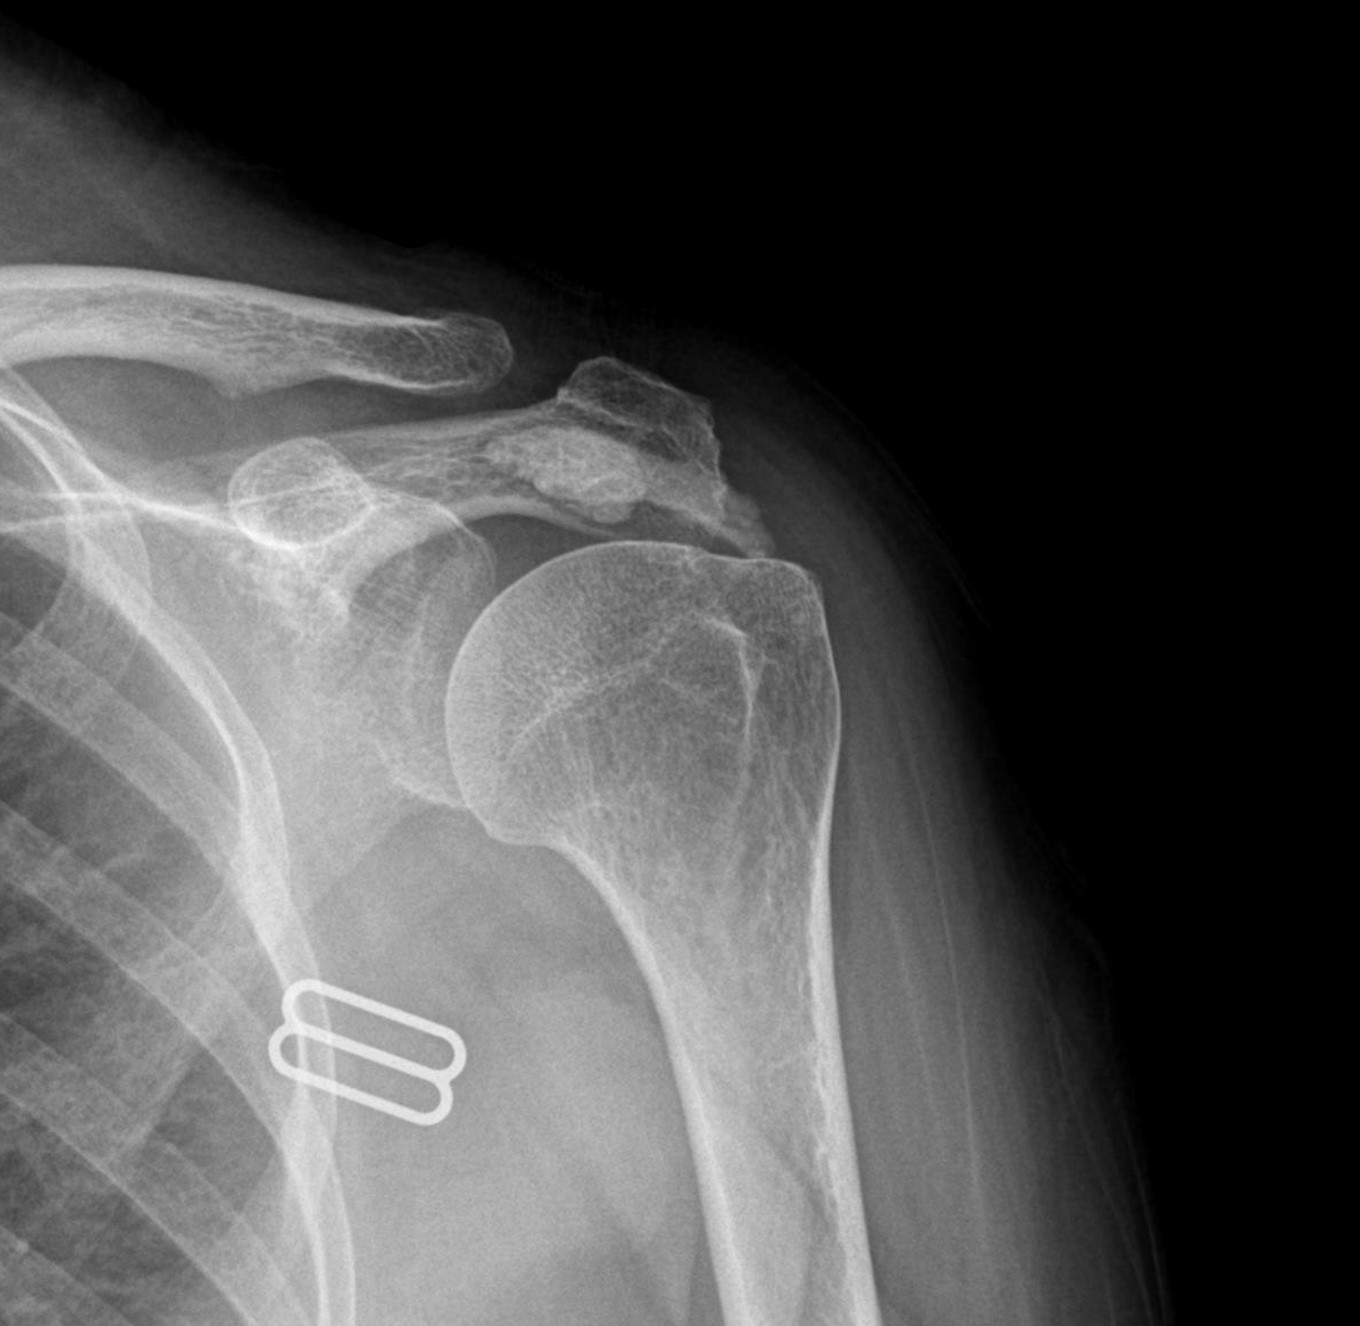

케이스 1: 형성기 단단한 석회 (1회 제거)

환자: 50대 남성, 우측 어깨 통증 8개월

시술 전:

X-ray에서 약 1.5cm 크기의 석회 확인

형성기 석회 (매우 단단)

타 병원에서 "수술 권유" 받음

시술 후:

1회 분쇄흡입술로 완전 제거

시술 직후 X-ray에서 석회 없음 확인

타 병원 시술 실패 원인 분석

환자분이 가져오신 이전 병원의 영상 자료를 검토했습니다.

문제점:

1세대 방법 사용: 주사바늘로 찌르고 씻어내는 방식

단단한 석회: 형성기~휴지기 석회였음

인대 손상: 반복 시술로 인대 주변 염증 발생

석회 잔존: 3회 시술 후에도 석회 대부분 남아있음

플래티넘에서의 치료

진단:

X-ray: 약 1.3cm 석회 (휴지기)

초음파: 석회 주변 인대 염증 소견

시술:

상완신경총 차단 마취

석회분쇄흡입술 시행

시술 시간: 35분

결과:

시술 직후 X-ray에서 석회 완전 제거 확인

기존 인대 염증은 재생주사로 추가 치료